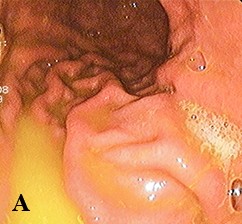

Проведена ЭГДС. Сразу при входе в желудок визуализировался волосяной шар (см. рис. 2а), при инсуффляции просвет желудка открывался мало. В теле желудка просвет заполнен волосяным образованием, которое продолжалось в антральный отдел. Слизистая оболочка не просматривалась, так как безоар почти полностью заполнял просвет. Далее он плотно входил в привратник, который с трудом удалось пройти эндоскопу. В просвете двенадцатиперстной кишки безоар тоньше, продолжался в тощую кишку.

Заключение: трихобезоар желудка и тонкой кишки. Синдром Рапунцель.

Проведены лапаротомия, гастротомия. Удаленный безоар имел форму слепка желудка. По консистенции и внешнему виду напоминал плотный войлок, обладал гнилостным запахом, длина его хвоста составила около 50 см (см. рис. 2б).